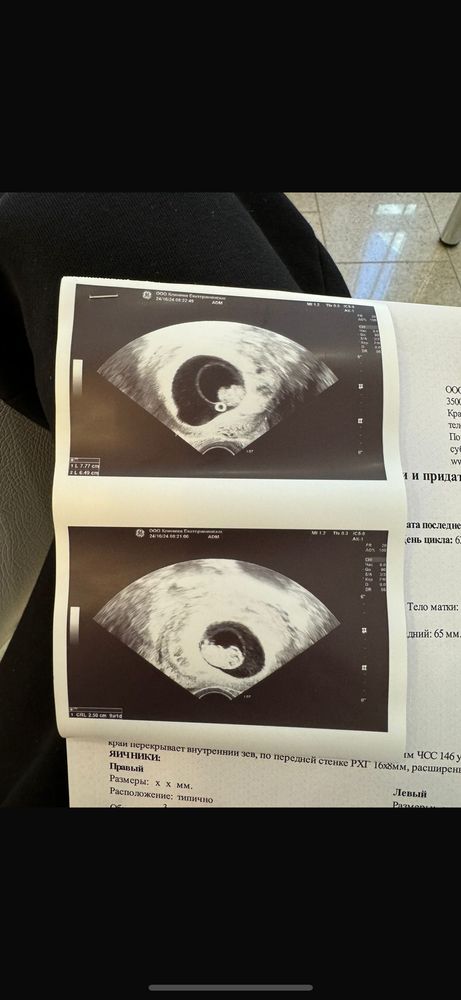

Результаты УЗИПривет, съездила я к своему репродуктологу, гематомка есть, совсем не большая, она говорит,что вряд ли это она мажет,и ребёнку она точно не мешает, у меня низкое прикрепление, хорион перекрывает внутренний зев, за счет роста матки хорион надрывается и это кровавый процесс, сказала не переживать,вести обычный образ жизни исключить только силовой спорт и секс, ребёнка она назвала «смотри какой пузатенький» а в сравнении с узи дочкой в 9 недель и с узи с сыном,он реально пузатый😀в доказательство и на память фото прилагаю 😀